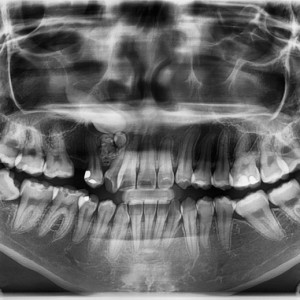

Pediatric dentistry 25 February 2026